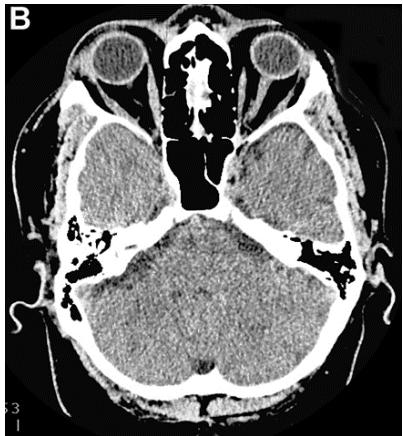

Figure 4: Same patient P., 75 years old, female TDR-3.

A. Cerebral CT before transcatheter intracerebral laser PBMT: Total atrophy of the temporal lobes is $40\%$ of the total tissue volume (TDR-3). B. Cerebral CT 12 months after transcatheter intracerebral laser PBMT: Reduction of the total atrophy of the temporal lobes by $12\%$. The patient is transferred to AD group in TDR-2 stage.

Accordingly, 5 (71.43%) patients were transferred to TDR-2 group, 2 (28.57%) patients remained in TDR-3 group (Table 2).

According to the results of digital processing of CT and MRI images one year after the treatment, all 7 (100%) patients had a decrease in the atrophy of the cerebral temporal lobes. It was accompanied by narrowing of the Sylvian fissures and subarachnoid space. Of these, 5 (71.43%) patients had a 10-12% decrease (Figures 4A, 4B), and 2 (28.57%) a 6-8% decrease.